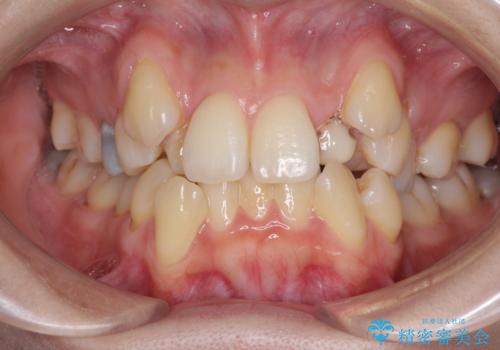

[ 矯正と補綴、総合歯科治療 ] クロスバイトを避ける前歯部審美ブリッジ

![[ 矯正と補綴、総合歯科治療 ] クロスバイトを避ける前歯部審美ブリッジの症例 治療前](https://seimitsushinbi.jp/wp/wp-content/uploads/2021/07/IMG_9914-500x350.jpg?v=1626697179)